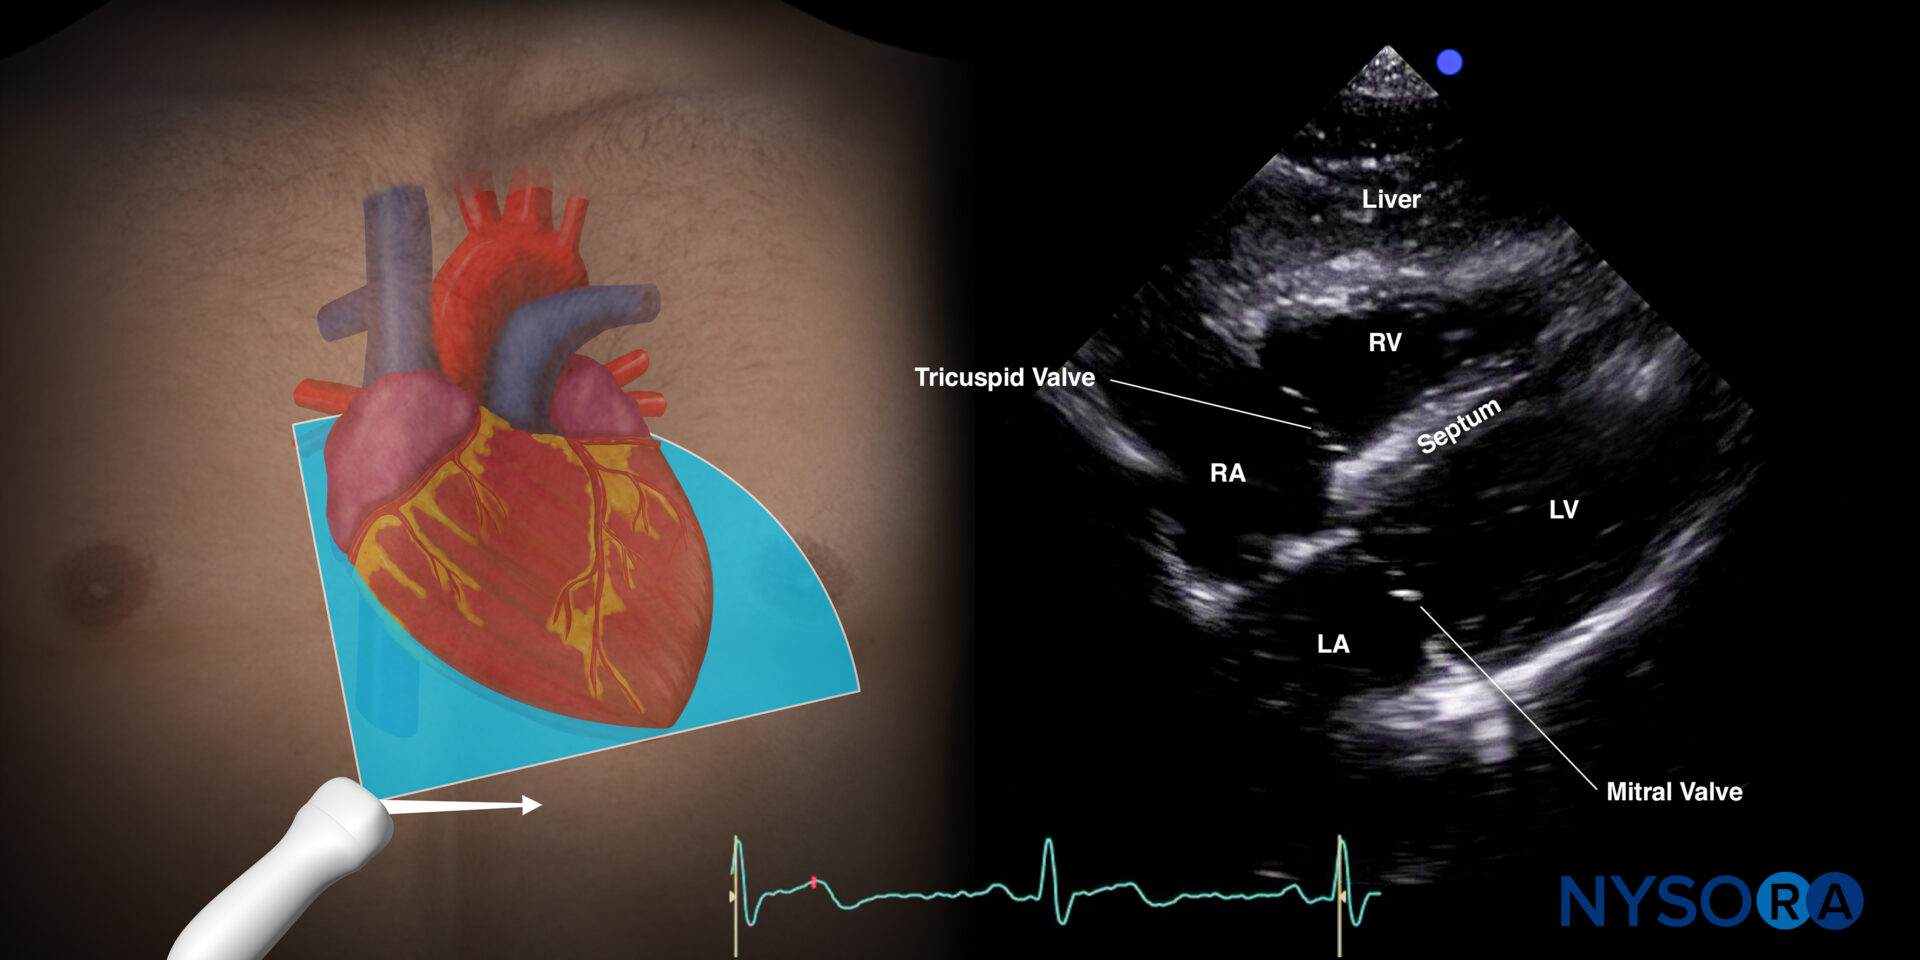

Subcostal or cardiac (four-chamber view)

This view will allow the user to rule out pericardial effusion or tamponade.

- Place the transducer with an overhand grip at the subcostal position with the transducer almost parallel to the skin and the index marker toward the patient’s right. The goal is to identify hypoechoic fluid surrounding the myocardium.

Normal sonoanatomy:

Sonoanatomy of the heart in the subcostal four-chamber view. Left atrium (LA), left ventricle (LV), right atrium (RA), right ventricle (RV), septum, tricuspid valve, mitral valve.

Reverse Ultrasound Anatomy of the heart in the subcostal four-chamber view. Left atrium (LA), left ventricle (LV), right atrium (RA), right ventricle (RV), septum, tricuspid valve, and mitral valve.